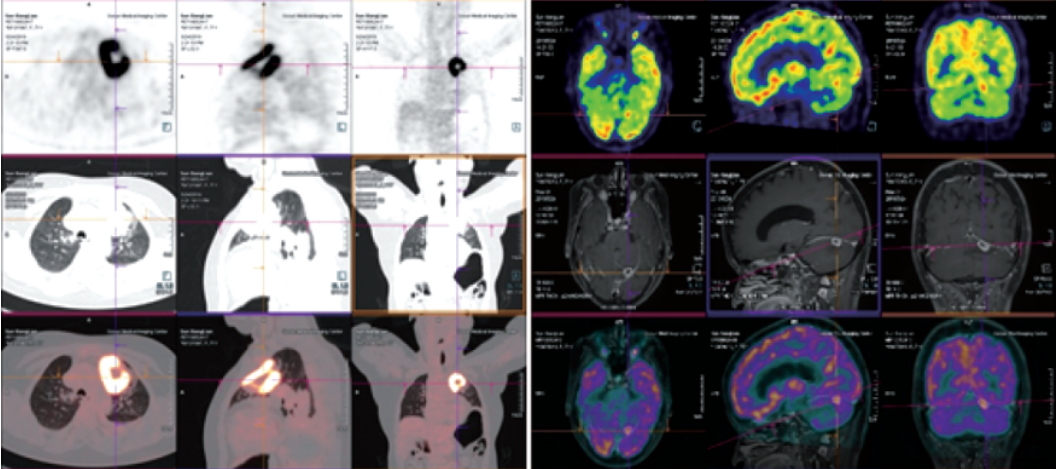

Biograph mCT Flow

?PET/CT在全身腫瘤的早期篩查、早期診斷及良惡性鑒別上、惡性腫瘤的分期、分級、尋找腫瘤原發(fā)病灶、評估療效及監(jiān)測腫瘤復(fù)發(fā)等具有重要價(jià)值。

?精準(zhǔn):本設(shè)備是新一代PET/CT,圖像重建矩陣可達(dá)400×400,其分辨率達(dá)到毫米級;其FlowMotion掃描技術(shù)提供極精細(xì)器官細(xì)節(jié)顯示,并對病灶提供可重復(fù)定量分析;顯著提高了微小病灶的檢出和確診率。

案例圖